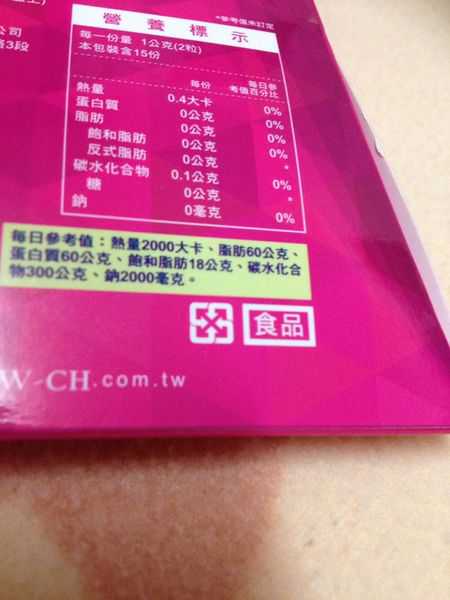

每一盒Supercut塑魔纖立塑膠囊都有三小包,每一小包有10顆膠囊

Supercut塑魔纖立塑膠囊的成分有:瓜拿那萃取粉、肉桂萃取粉、辣椒萃取物(唐辛子)、吡啶甲酸鉻、番瀉葉粉末、玉米澱粉、氧化鎂、二氧化矽。

食用方式:早晚餐前30分鐘各1粒,每日不超過2粒。(多食無益)

番瀉葉萃取物每日食用限量為12mg以下,

番瀉葉萃取物每日食用限量為12mg以下,